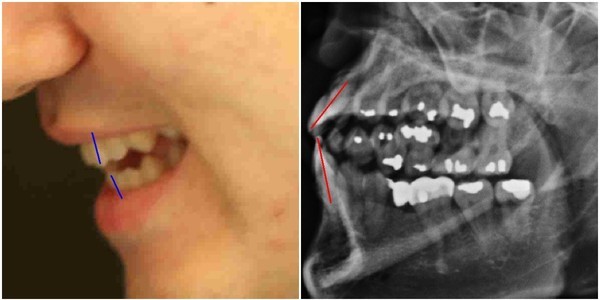

① 박주신씨의 신체를 촬영한 것으로 알려진 3개의 엑스레이(공군훈련소-자생병원-비자발급용)를 비교·판독한 결과 나타나는 ‘석회화 현상’-‘극상돌기’-기도와 폐의 기관지를 연결하는 ‘기관(氣管)’의 뻗은 모양-'흉곽 형태'의 차이.

③ 박주신씨의 치아가 보이는 엑스레이 분석결과(20대 청년의 것으로 볼 수 없는 매우 불량한 치아상태).

- ▲ 양승오 박사 등 피고인들이 유력한 증거로 들고 있는 박주신씨 명의의 3개의 엑스레이. 왼쪽부터 공군훈련소(2011년 8월)-자생병원 엑스레이(2011년 12월)-비자발급용 엑스레이(2014년 7월). ⓒ 뉴데일리DB

영상의학전문의인 양승오 박사(동남권원자력의학원 암센터 핵의학과 주임과장)와 치과의사 김우현 원장 등 이 사건 피고인들은, 박주신씨 명의의 MRI와 엑스레이 사진을 근거로, 병역비리의혹을 제기하고 있다.

박주신씨 명의의 치아엑스레이는 이 사건 피고인들이, 주신씨 명의의 흉부엑스레이와 함께, ‘대리신검’ 혹은 ‘영상자료 바꿔치기’ 의혹의 주요 증거로 꼽고 있는 영상자료다.

주신씨가 자생병원에서 촬영한 것으로 알려진 이 치아엑스레이에 대해 피고인들이 강한 의문을 나타내는 이유는, 엑스레이 속 치아의 상태가 도저히 20대 중반 청년의 것이라고는 보기 힘들만큼 불량하기 때문이다.